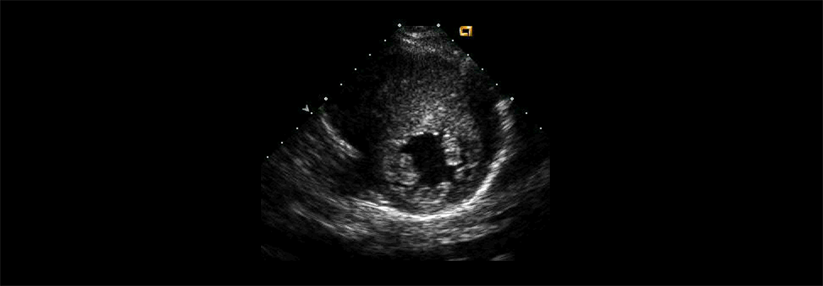

Die hypertrophe Kardiomyopathie ist definiert als Verdickung des Myokards auf mindestens 15 mm ohne mechanische Belastung. In vielen Fällen stecken genetische Ursachen dahinter, bei einem Drittel der Patienten kennt man die Genese aber nicht.

Vielfach handelt es sich bei dieser Kardiomyopathie um einen asymptomatischen Zufallsbefund, erklärte Prof. Dr. Roman Pfister von der Klinik III für Innere Medizin an der Universitätsklinik Köln. Doch rund 40 % der Betroffenen entwickeln eine progressive Herzinsuffizienz, vorwiegend durch eine Obstruktion im linksventrikulären Ausflusstrakt (LVOT). Sie stellt therapeutisch das größte Problem dar.